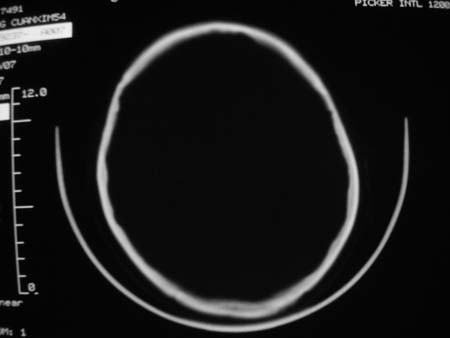

男,54岁,十天前被钢管打伤头顶部,现自述头部不适,视物模糊,并于两天前发觉右枕部有包块,既往未有明显异常.

颅骨多处骨质不完整,内板变薄,右侧额颞部局部呈“穿凿样”骨质缺损,相应区硬膜外密度略增高。多考虑:骨嗜酸性肉芽肿!

颅骨多处骨质不完整,内板变薄,右侧额颞部局部呈“穿凿样”骨质缺损,相应区硬膜外密度略增高。多考虑:骨髓瘤或骨嗜酸性肉芽肿!

颅骨多处骨质不完整,内板变薄,右侧额颞部局部呈“穿凿样”骨质缺损,缺损骨质边缘锐利无硬化,相应区硬膜外密度略增高。多考虑:骨嗜酸性肉芽肿!

颅骨多处骨质不完整,内板变薄,右侧额颞部局部呈“穿凿样”骨质缺损,相应区硬膜外密度略增高。多考虑:骨髓瘤或骨嗜酸性肉芽肿!10天前受伤,不会在2天前才发现头部包块,估计与外伤无关.